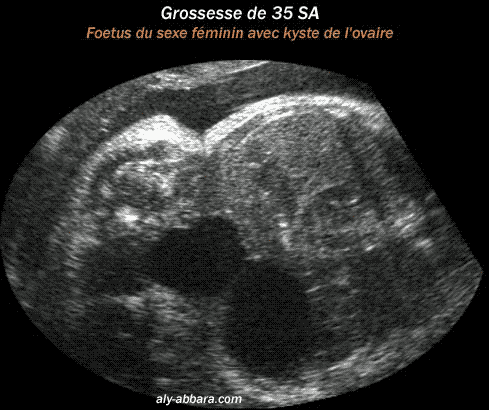

Kyste Ovarien Chez Un Foetus Du Sexe Feminin

Kyste De L Ovaire Fœtal

Kyste De L Ovaire Foetal Bilateral Et Regressif In Utero

Kyste De L Ovaire Fœtal Bilateral Et Regressif In Utero